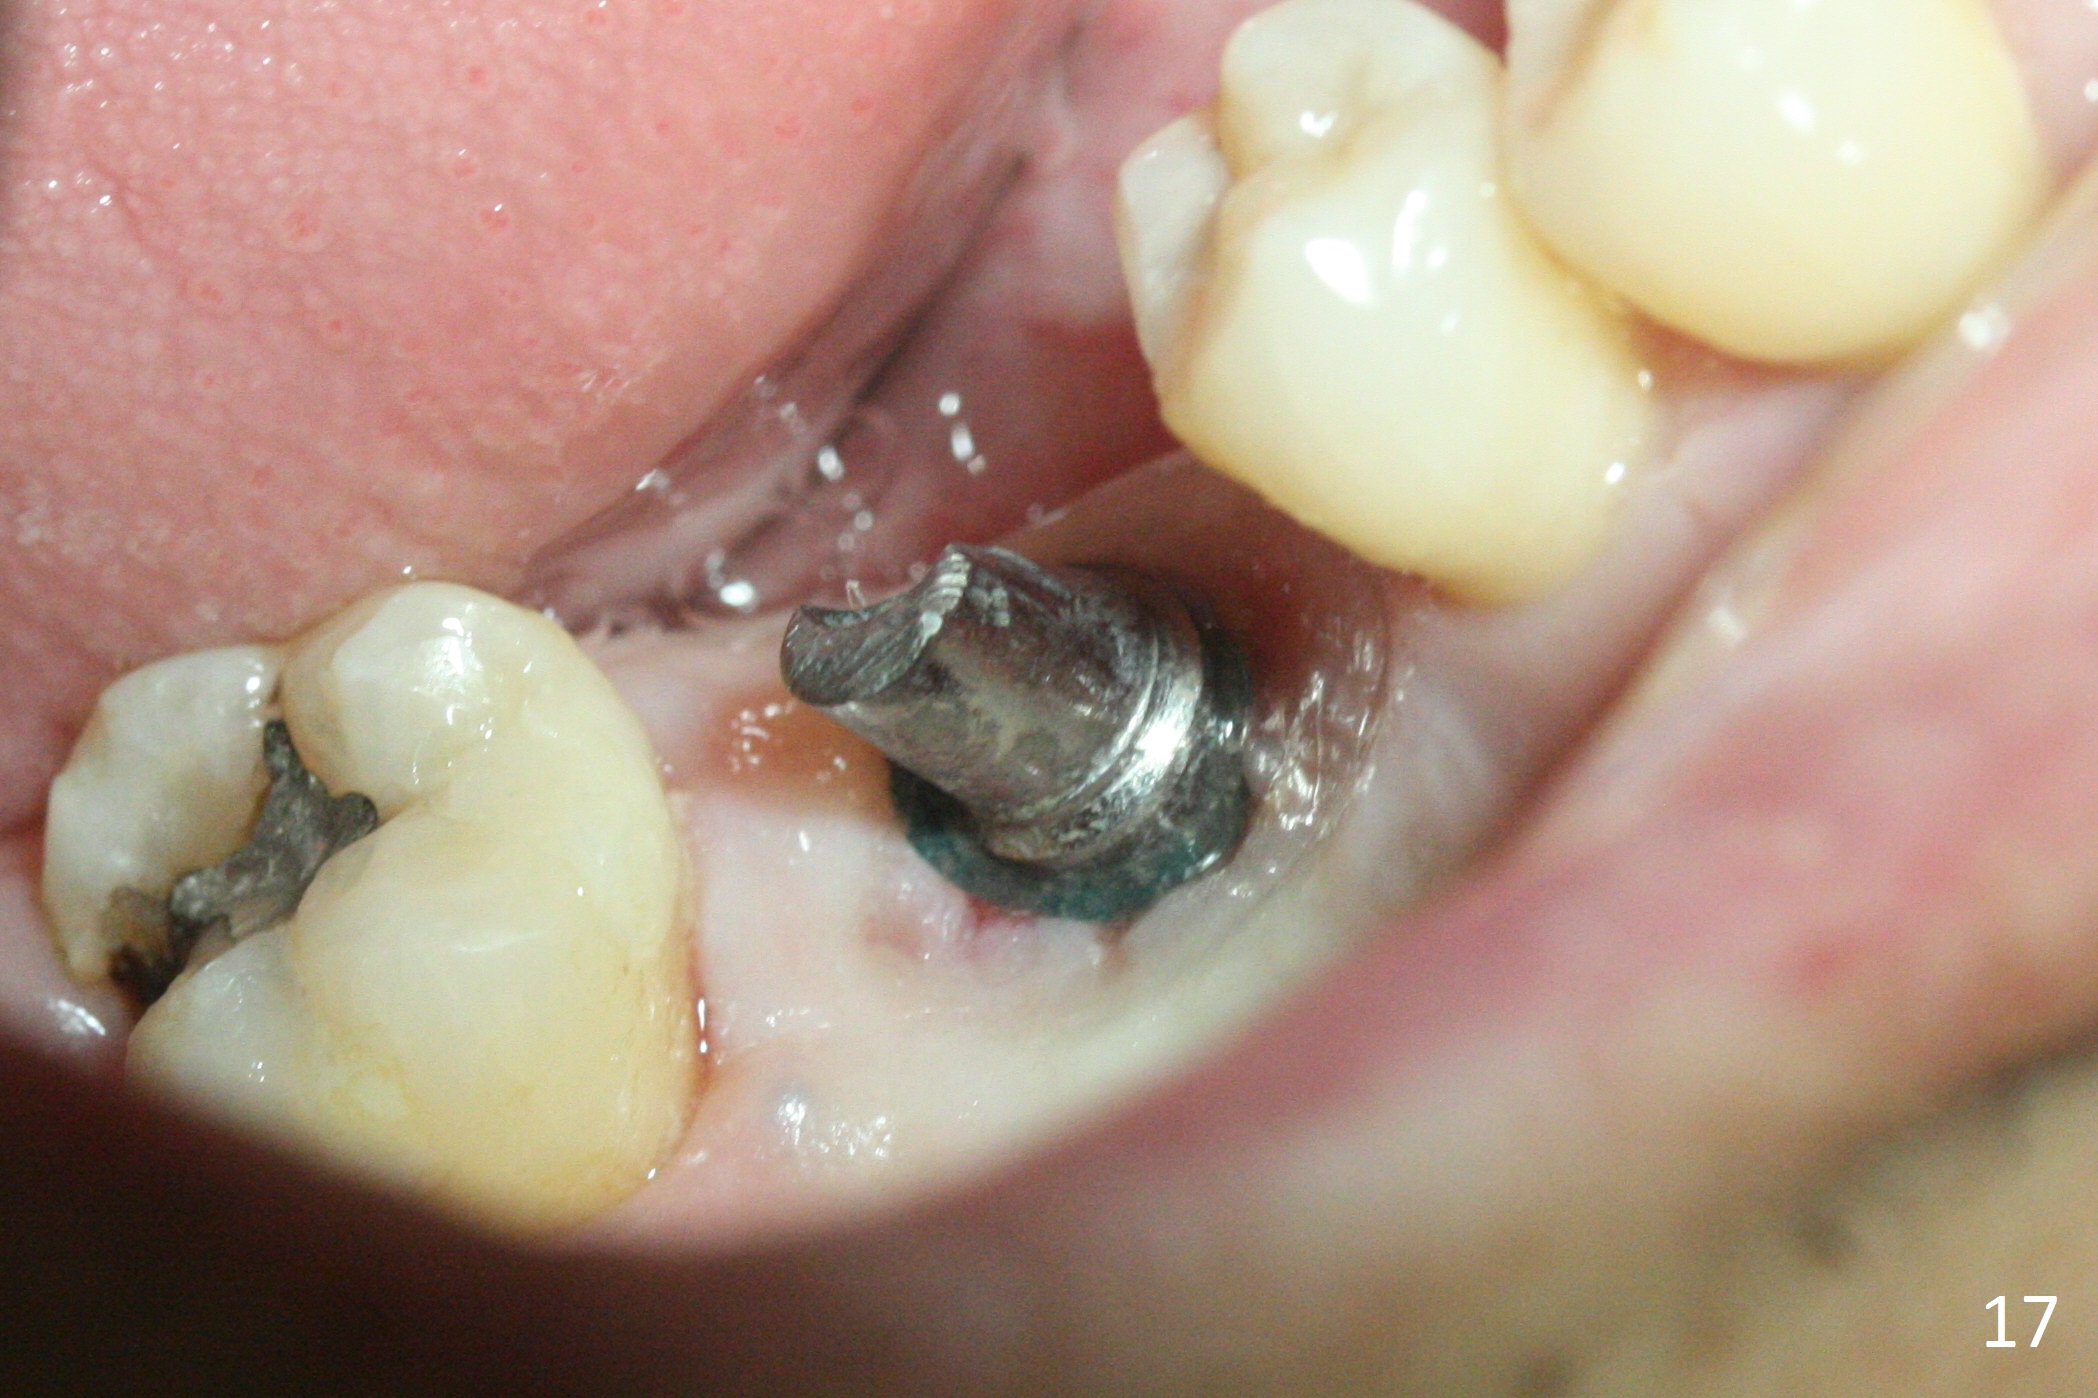

Implant threads appear to have been covered by bone coronally (Fig.15 *) and apically (<) 5 months postop. The provisional remains in place (Fig.16), although dislodged twice and replaced by the patient. The gingiva around the provisional and abutment is healthy (Fig.17 after packing with gingival retraction cord for impression).